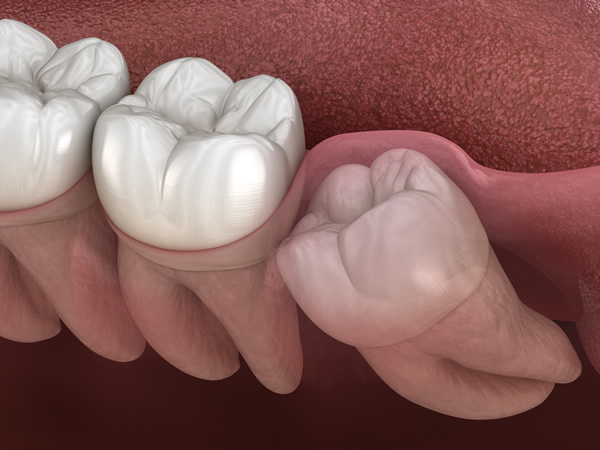

中でも、歯ぐきの中に埋もれている「埋伏歯(まいふくし)」は、専門的な技術と慎重な処置が求められます。

斜めに生えたり、隣の歯を圧迫している場合や、埋まったまま(埋伏歯)炎症を繰り返すケースでは、抜歯をおすすめします。

横向きに埋まっている「水平埋伏歯」は、手前の歯を強く押すことで、痛みや歯並びの乱れ、虫歯や歯周病の原因になることがあります。

放置すると、隣の歯の根が失われたり、神経を傷つけたりするリスクもあるため、早めの対応が大切です。また、水平埋伏歯は骨や神経のすぐ近くに位置していることが多く、抜歯には高い技術力が求められます。